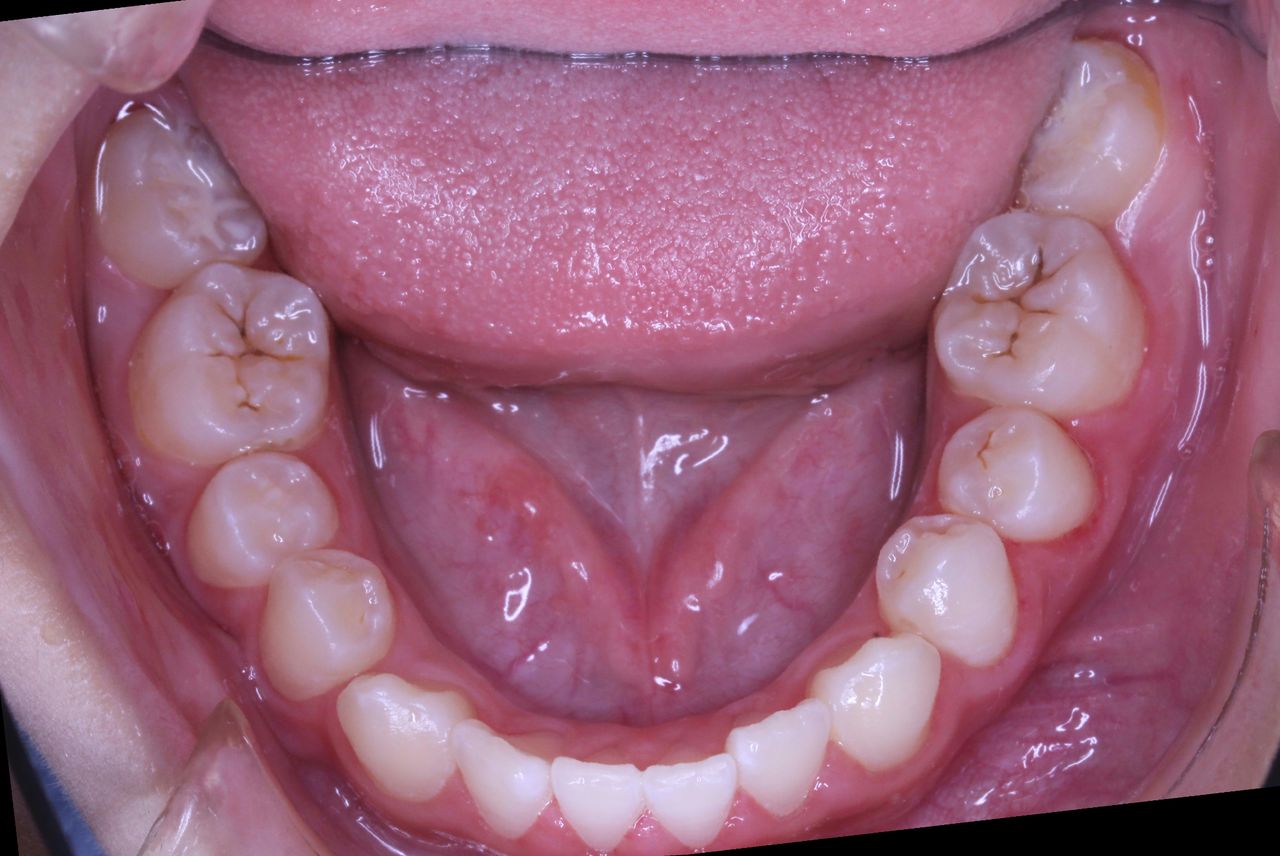

上顎も下顎もそこそこの歯列になっていると思います。

咬み合わせも良好です

なんと、大人の歯は虫歯0本で管理されてます!